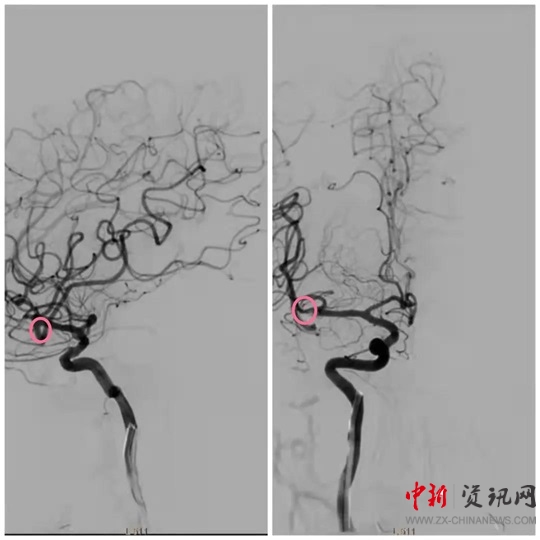

經(jīng)過一系列的術(shù)前準備并經(jīng)患者家屬同意后,立即繞行病房進入介入手術(shù)室,實施緊急手術(shù)。卒中中心團隊、胸痛中心團隊和介入團隊密切配合,為患者分別實施了腦動脈造影+主動脈弓造影+顱內(nèi)動脈瘤栓塞術(shù)+冠狀動脈造影術(shù)+經(jīng)皮冠狀動脈支架植入術(shù),成功把患者從死亡邊緣拉回。目前,患者病情穩(wěn)定,各項指標良好。

(動脈瘤栓塞后)